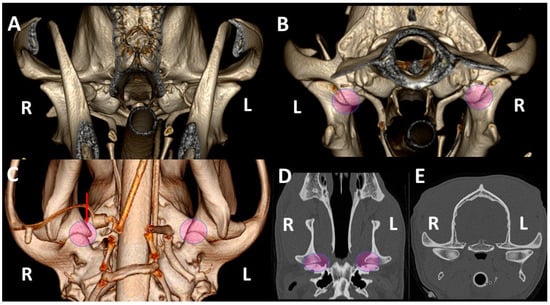

3.1. A Detailed Description of the Bone Anatomy of TMJ Using 3DVR Images

3.2. Comparison by 3DVR of TMJs in Each Dog, According to Skull Type and Age

3.3. A Detailed Assessment of Each TMJ Comparing 3DVR Images with the Three Standard CT Planes

3.4. A Pictorial Essay of 3DVR Images in Some Pathological Cases